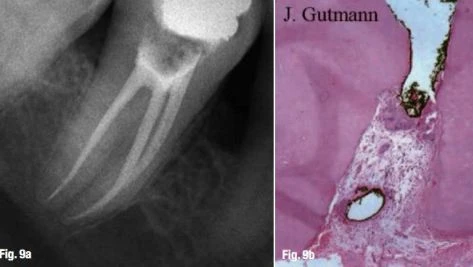

Ngay cả khi chưa có tổn thương quanh chóp. Một vài đồng nghiệp tán thành rằng điểm chóp cuối cùng nằm tại vị trí lỗ chóp sinh lý. Vị trí này bảo tồn nguyên vẹn hình thái chóp răng, và không làm hại đến lỗ chóp chân răng cũng như dây chằng nha chu, vì vậy cho phép lành hương tối ưu (Hình 9a & b). Các đồng nghiệp khác đề nghị rằng điểm chóp cuối cùng nằm tại lỗ chóp giải phẫu, đôi khi nằm ngay chóp răng, hoặc thậm chí ngay chóp răng trên X-quang. Cách làm này chấp nhận khái niệm chóp mở (apical patency) hay kỹ thuật làm sạch chóp (apical clearing technique) (Hình 10a & b).

điểm thắt chóp sinh lý

Hình 9a & b: Điểm chóp cuối cùng nằm tại lỗ chóp sinh lý: hình ảnh X-quang sau 12 tháng (a); sự lành thương tốt (b).